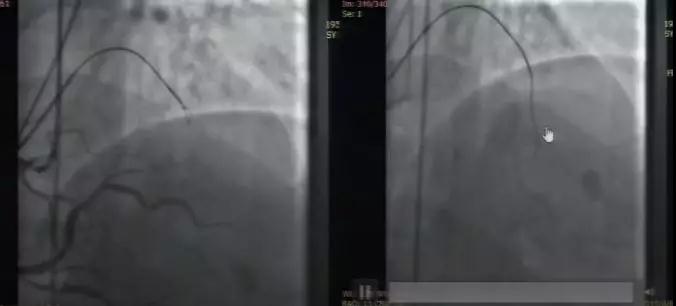

在超声确认这个闭塞段开口为正确开口后,Corsair抵近闭塞开口,XT头部做成两个小弯,逐步、耐心地做小弯进行Knuckle,反复推送后。导丝Knuckle前进,发现局部斑块较硬,造影可见Knuckle环走行正确。

Knuckle导丝再推进受阻,跟进Corsair,交换UB3寻找真腔,成功进入远端血管结构内。这样,在真腔启动的Knuckle导丝协助找到了正确的血管结构,再通过传统的正向平行导丝技术成功进入真腔

LAD的CTO病变,逆向条件较差,正向导丝和平行导丝均在假腔,但方向正确。微导管退回闭塞段起始1mm,启动Knuckle。多体位确认Knuckle走行在血管结构内,在闭塞末端,跟进微导管,重新做正向导丝。后确认导丝走行在假腔,但在血管结构内,启动ADR,Stingray球囊到达穿刺点,造影确认穿刺方向。而后应用Conquest pro12穿刺成功,结果满意。